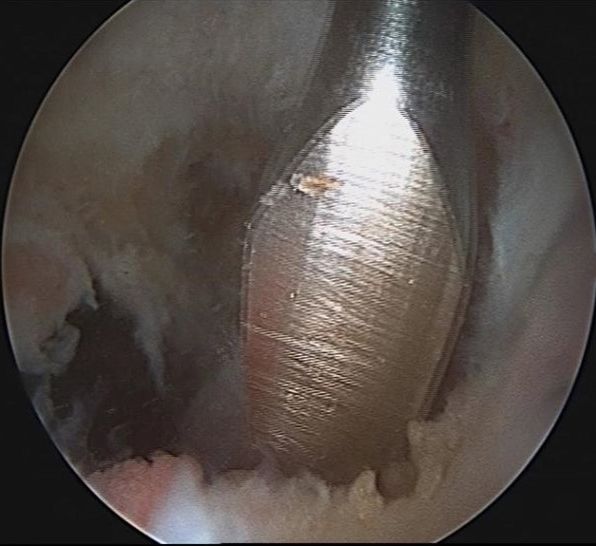

Now the 30° optic is changed to 70° optic for better visualization of the posterior slope of the tibia to evaluate the insertion side of the PCL. An 18-gauge needle is inserted from posteromedial to evaluate the correct entry point for inserting the working cannula. Following the posterior incision, the 7mm cannula is inserted and fixed by a suture. From the posteromedial portal under direct visualization with the 70° scope debridement of the PCL remnants is carried out from anteromedial (Fig 18).

Fig 18 - Arthroscopic release of tibial PCL remnants